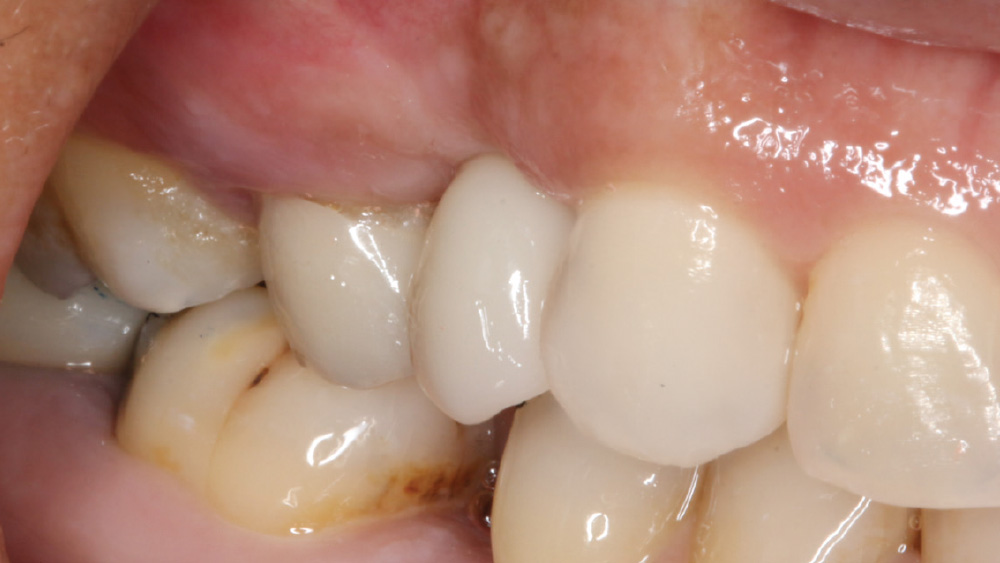

CASE REPORT

The following case, which I performed alongside Dr. Stephanie Tilley of Pensacola, Florida, illustrates the use of both surgical techniques for the same patient, who presented with edentulous spaces in the areas of both right and left maxillary first bicuspids. Due to varying soft-tissue volume on each side of the arch, implant surgery was performed using a flapless procedure for one site, while the attached gingiva was reflected to expose the available hard tissue for the other. As a result of proper site evaluation, treatment planning and restorative-driven implant placement, both surgical techniques led to successful outcomes for the patient.